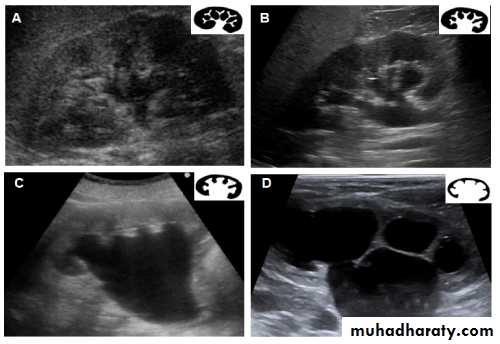

Classification of hydronephrosis in grade I–IV.

• Hydronephrosis grade I: dilatation of the renal pelvis without dilatation of the calices without signs of parenchymal atrophy. • Hydronephrosis grade II: dilatation of the renal pelvis and calices. No signs of parenchymal atrophy. • Hydronephrosis grade III: Minor signs of organ atrophy present (flat papillae and blunt fornices).• Hydronephrosis grade IV: massive dilatation of the renal pelvis and calices. Significant signs of renal atrophy (thin parenchyma).